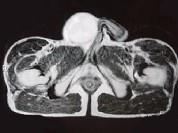

29岁男性患者,右侧睾丸肿痛5个多月,行MRI检查,如图所示,T1加权见右侧阴囊内见球形肿块,呈中等信号,其内信号不均,T2加权肿块为高信号,最可能的结果...

问题 29岁男性患者,右侧睾丸肿痛5个多月,行MRI检查,如图所示,T1加权见右侧阴囊内见球形肿块,呈中等信号,其内信号不均,T2加权肿块为高信号,最可能的结果是()

选项 A.精原细胞瘤 B.睾丸结核 C.畸胎瘤 D.皮样囊肿 E.畸胎癌

答案 A